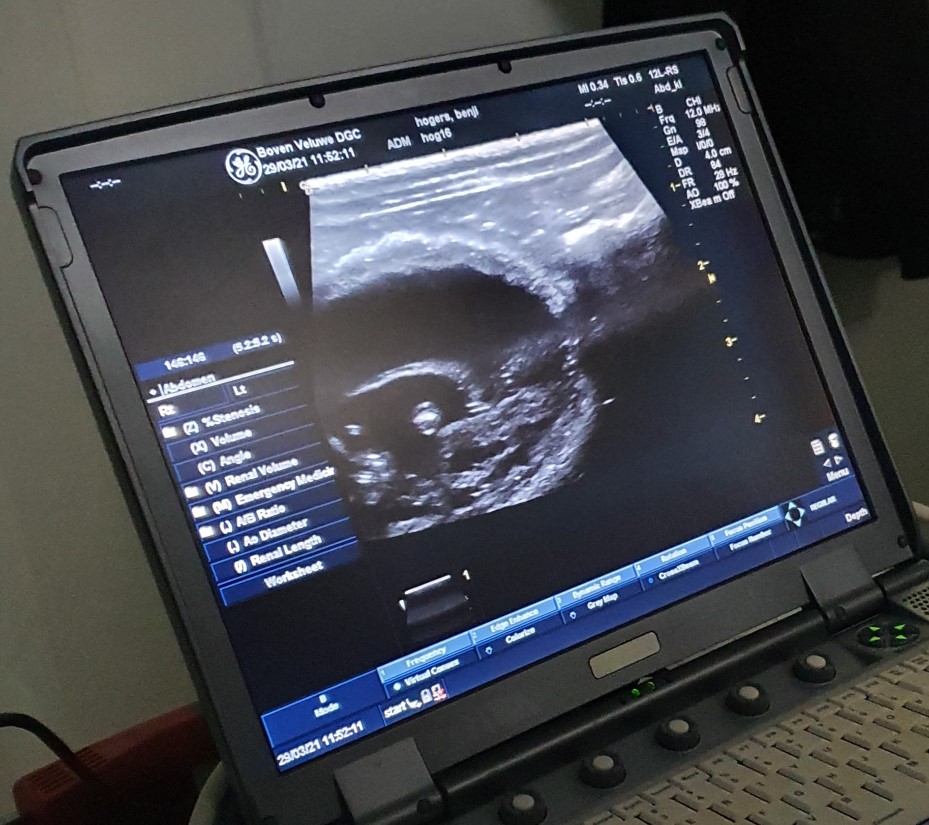

hier zie je het meten van een schedeltje

van een kitten, je ziet dat het beeld meer ingezoomd is, dit is met de

tweede "kop" van het echo apparaat gedaan. Veel meer detail, maar ook

lastiger om alles goed in beeld te krijgen door de bewegingen |

hier het meten van een ander kitten, je kan de 2

hersenhelften zien, de opening van het neusbeen en de contouren van het

lichaam |

De echo is gemaakt met een apparaat uit het humane

ziekenhuis. De beelden zijn dan ook met een 2 verschillende koppen

gemaakt, waardoor er ook heel gedetailleerde beelden zijn.